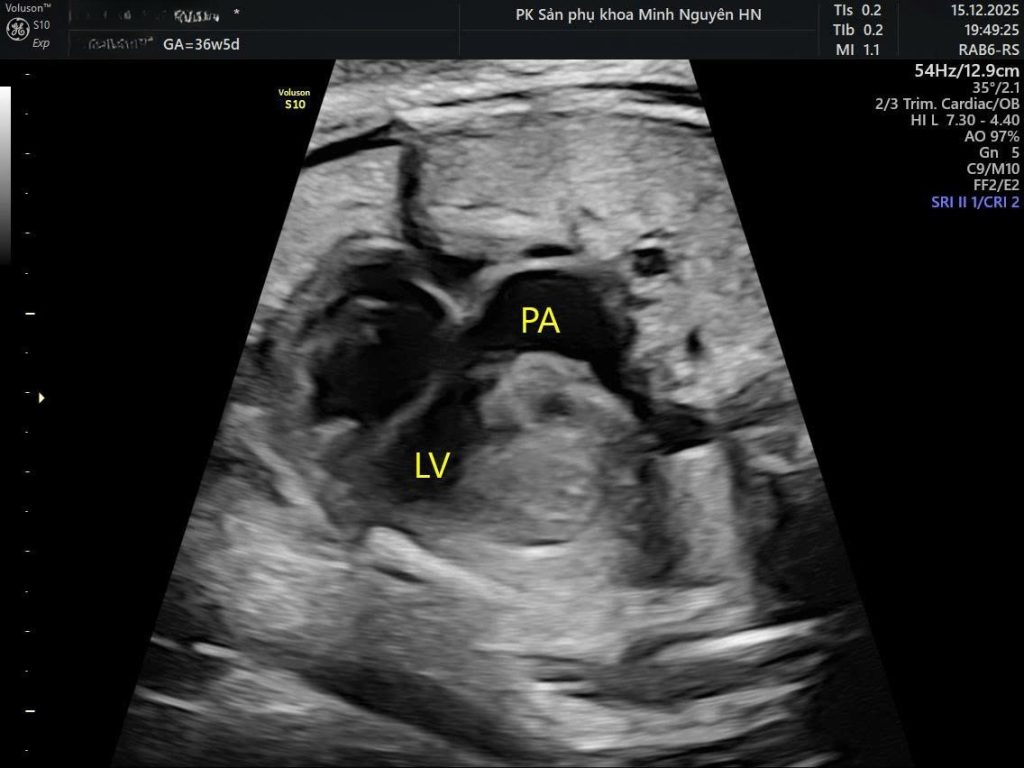

Ở tim bình thường, hai đại động mạch bắt chéo nhau tạo hình chữ X. Trong chuyển vị đại động mạch hoàn toàn (d-TGA), hai mạch này chạy song song tạo hình chữ I.

Trong TGA sẽ thấy hai mạch chạy song song (I-sign).

Bình thường sẽ thấy hai đại động mạch bắt chéo nhau (X-sign).

Dấu hiệu quyết định nằm ở:

- Mặt cắt đường ra hai thất

- Mặt cắt ba mạch máu và khí quản